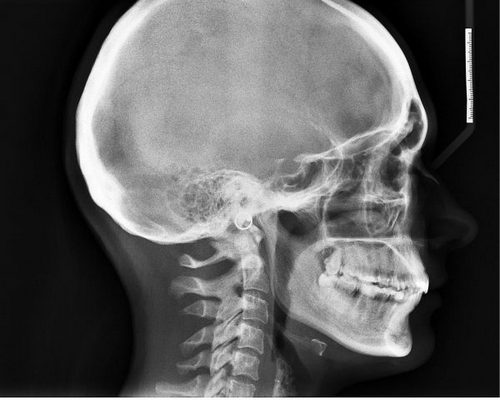

Безусловно, перед началом лечения крайне важно пройти профессиональную диагностику. С ее помощью удастся точно выяснить, с чем именно приходится иметь дело. Не стоит самостоятельно принимать медикаменты, потому как они могут оказаться неэффективны. Курс лечения должен быть назначен в зависимости от ситуации. Например, врач может направить пациента на МРТ и КТ. Эти исследования являются достаточно информативными и позволяют выявить многие патологии мозга. Также нередко назначают рентген, он особенно полезен в случае травм головы.

- компьютерная ренгеновская томография: наиболее точный метод диагностирования патологий органов и систем в человеческом теле. Сегодня КТ часто применяют для установления каких-либо отклонений в работе головного мозга. Методика, во-первых, безопасна, а во-вторых, очень точна. С ее помощью обнаруживаются опухоли и другие новообразования в черепе, устанавливаются любые проблемы с кровообращением в церебральных сосудах или угнетением ЦНС. После процедуры врач получает четкое изображение костей, мозговых оболочек и артерий.

- магнитно-резонансная томография: альтернатива КТ, когда рентген противопоказан. Наиболее часто к МРТ прибегают, чтобы установить локализация и размеры новообразований в черепе, проверить состояние мозга до и после операции, понять, отчего у человека возникают приступы головной боли, обмороки. МРТ фактически дает врачу полное представление о состоянии всех мозговых структур;